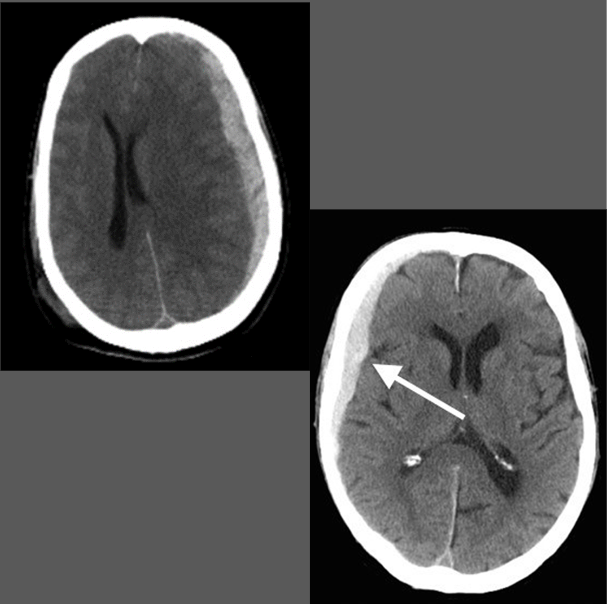

What is this pathology?

Subdural Hematoma